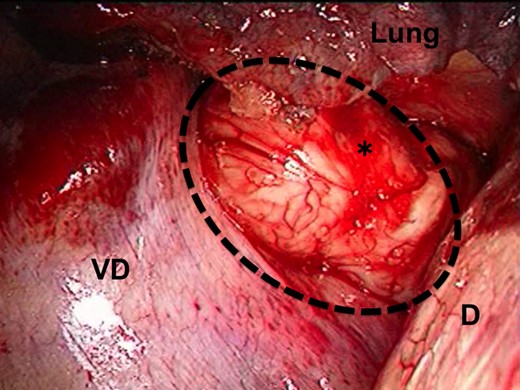

A 62-year-old male was found to have a well-demarcated mass with a smooth surface at the right side of the lower esophagus by chest computed tomography (CT) upon medical check-up (Fig. 1). Routine laboratory data and the serum levels of tumor markers were within normal limits. Positron emission tomography (PET) revealed the accumulation of 18F-fluoro-2-deoxyglucose (FDG) at the tumor. The maximum standardized uptake value was 4.0, increasing to 4.8 in the late phase. Upper gastrointestinal endoscopy revealed no distinct mucosal abnormalities or no evidence of tumors. Endoscopic ultrasonography showed a mass ∼2 cm in diameter arising in the third layer 40 cm from the incisor teeth (Fig. 2a and b). These findings diagnosed the lesion as an esophageal submucosal tumor with suspecting an esophageal leiomyoma or GIST. Being under general endotracheal double-lumen anesthesia with split-lung ventilation, the patient was allowed to lie on the healthy side (left) and posture lateral decubitus. A 6-cm long access incision was made at the posterior axillary line in the 10th intercostal space. Two 10.5-mm ports were made at the seventh intercostal space in the anterior axillary line and other at the same intercostal space in the posterior axillary line. After no adhesion in the thoracic cavity was observed, the pulmonary ligament was dissected and the lower lobe of the right lung was moved anteriorly. A tumefactive lesion was found in the lower esophagus. An incision was made in the mediastinal pleura, and the mass was confirmed at the outer longitudinal muscle of the lower esophagus. The tumor was easily removed from the surrounding tissue by a tumor enucleation procedure. No esophageal mucosa was injured intraoperatively. The operation time was 118 min, and the blood loss was 11 g (Fig. 3). Macroscopic examination found that the removed white parenchymal mass was 29 × 20 × 14 mm in size. Histopathological examination showed that the specimens stained with hematoxylin and eosin-contained tumor cells, which had elongated oval nuclei and eosinophilic and spindle-like reticulum, were arranged in fascicles without mitosis. Immunohistochemical results were positive for c-KIT, S-100 protein, CD34 and vimentin, and the specimen was diagnosed as a low-risk GIST (Fig. 4a and b). The patient took an uneventful postoperative course, was allowed to remove the surgical drain after confirming the clinical status by esophagography on postoperative day 9, and discharged on postoperative day 13. At 6 years after surgery, the patient was found to be healthy without tumor recurrence.

Thoracoscopic view of the tumor. The image shows bulging through the right thoracic cavity. The black dash line and asterisk indicate the GIST; D, the diaphragm; VD, the vertebral body.